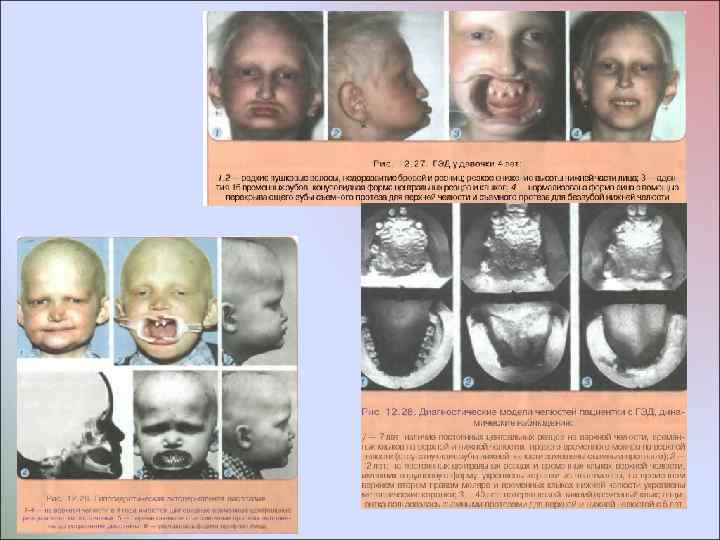

Врожденное отсутствие более 10 постоянных зубов У некоторых пациентов отмечают врожденное множественное отсутствие зубов без изменения развития других производных эктодермы У пациентов с ГЭД мало волос, они светлого цвета, брови недоразвиты, ресницы растут кустиками; кожа сухая, морщинистая, нередко пигментированная вокруг глаз и рта; ногти деформированы; зрение нарушено - пользуются очками с детства. По эстетическим отклонениям, состоянию психоневротического статуса и общим нарушениям организма пациенты этих двух групп различаются. Общим для них является лишь врожденное отсутствие зачатков более 10 постоянных зубов

Врожденное отсутствие более 10 постоянных зубов У некоторых пациентов отмечают врожденное множественное отсутствие зубов без изменения развития других производных эктодермы У пациентов с ГЭД мало волос, они светлого цвета, брови недоразвиты, ресницы растут кустиками; кожа сухая, морщинистая, нередко пигментированная вокруг глаз и рта; ногти деформированы; зрение нарушено - пользуются очками с детства. По эстетическим отклонениям, состоянию психоневротического статуса и общим нарушениям организма пациенты этих двух групп различаются. Общим для них является лишь врожденное отсутствие зачатков более 10 постоянных зубов

Перед началом ортодонтического лечения и зубопротезированием проводят обследование пациента, включающее: • Изучение фотографий лица с детского возраста для выявления смешений нижней челюсти, асимметрий лила, укорочения его нижней части • Сбор анамнеза, уточнение возрастного периода потери временных и постоянных зубов • Рентгенологический контроль (ОПТГ челюстей) -определение величины и локализации дефектов зубных рядов: наклонов, корпусного смешения соседних и противостоящих зубов, нарушений окклюзии зубных рядов, наличия и степени формирования всех постоянных зубов, рассасывания корней всех временных зубов • Изучение моделей челюстей, особенностей дефектов зубных рядов, формы и уровня расположения гребня альвеолярного отростка • Клиническое определение морфофункционального состояния зубочелюстной системы, в том числе ВНЧС

Перед началом ортодонтического лечения и зубопротезированием проводят обследование пациента, включающее: • Изучение фотографий лица с детского возраста для выявления смешений нижней челюсти, асимметрий лила, укорочения его нижней части • Сбор анамнеза, уточнение возрастного периода потери временных и постоянных зубов • Рентгенологический контроль (ОПТГ челюстей) -определение величины и локализации дефектов зубных рядов: наклонов, корпусного смешения соседних и противостоящих зубов, нарушений окклюзии зубных рядов, наличия и степени формирования всех постоянных зубов, рассасывания корней всех временных зубов • Изучение моделей челюстей, особенностей дефектов зубных рядов, формы и уровня расположения гребня альвеолярного отростка • Клиническое определение морфофункционального состояния зубочелюстной системы, в том числе ВНЧС